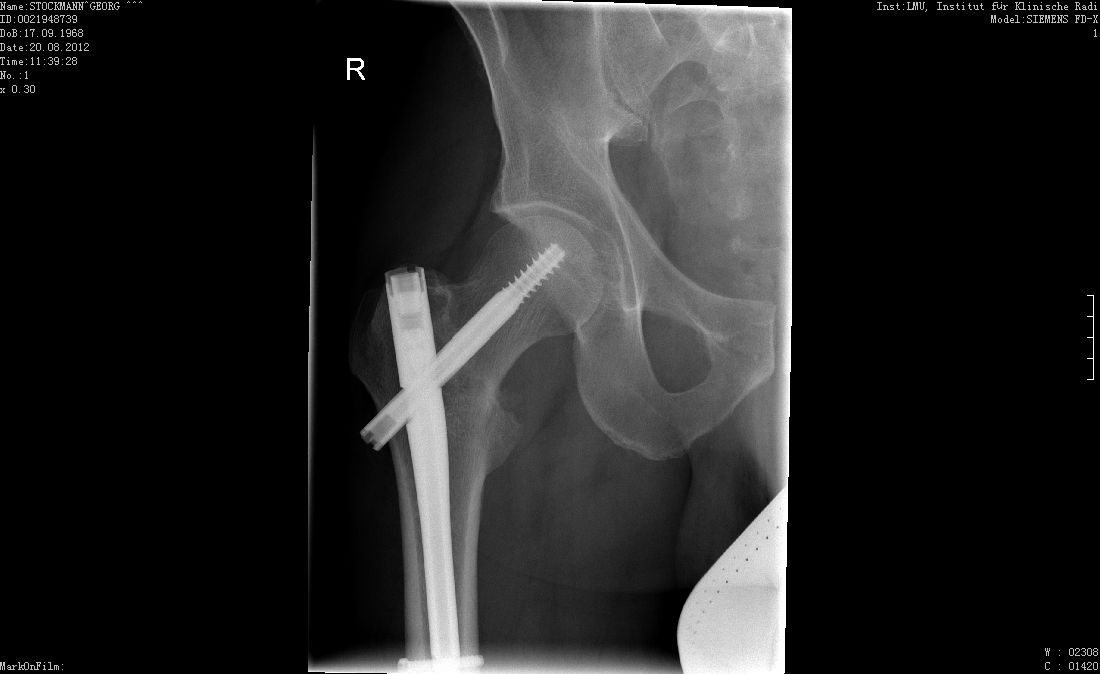

Screwed Veröffentlicht am August 21, 2012November 28, 2013 von artist Es wächst zusammen was zusammen gehört. Zeit das Fahrrad reparieren zu lassen … Veröffentlicht von artist Zeige alle Beiträge von artist